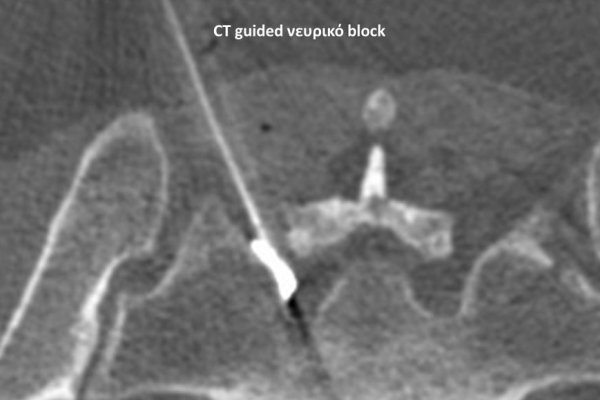

Με την βοήθεια της επεμβατικής ακτινολογίας είναι δυνατόν να πραγματοποιηθούν διαφορες ενέσιμες τεχνικές που αποσκοπούν στη μείωση του μυοσκελετικού πόνου, την ενίσχυση της αποτελεσματικότητας της φυσιοθεραπείας και την επιτάχυνση της διαδικασίας επούλωσης. Οι τεχνικές αυτές περιλαμβάνουν την κατευθυνόμενη έγχυση φαρμάκων ή πραγματοποίηση θεραπευτικών χειρισμών ακριβώς στη θέση τηςπαθολογία. Ετσι εξασφαλιζεται η μέγιστη αποτελεσματικότητα ( έως 95% κατά περίπτωση) και ασφάλεια σε σχέση με τυφλούς χειρισμούς χωρίς ακτινολογική καθοδήγηση.